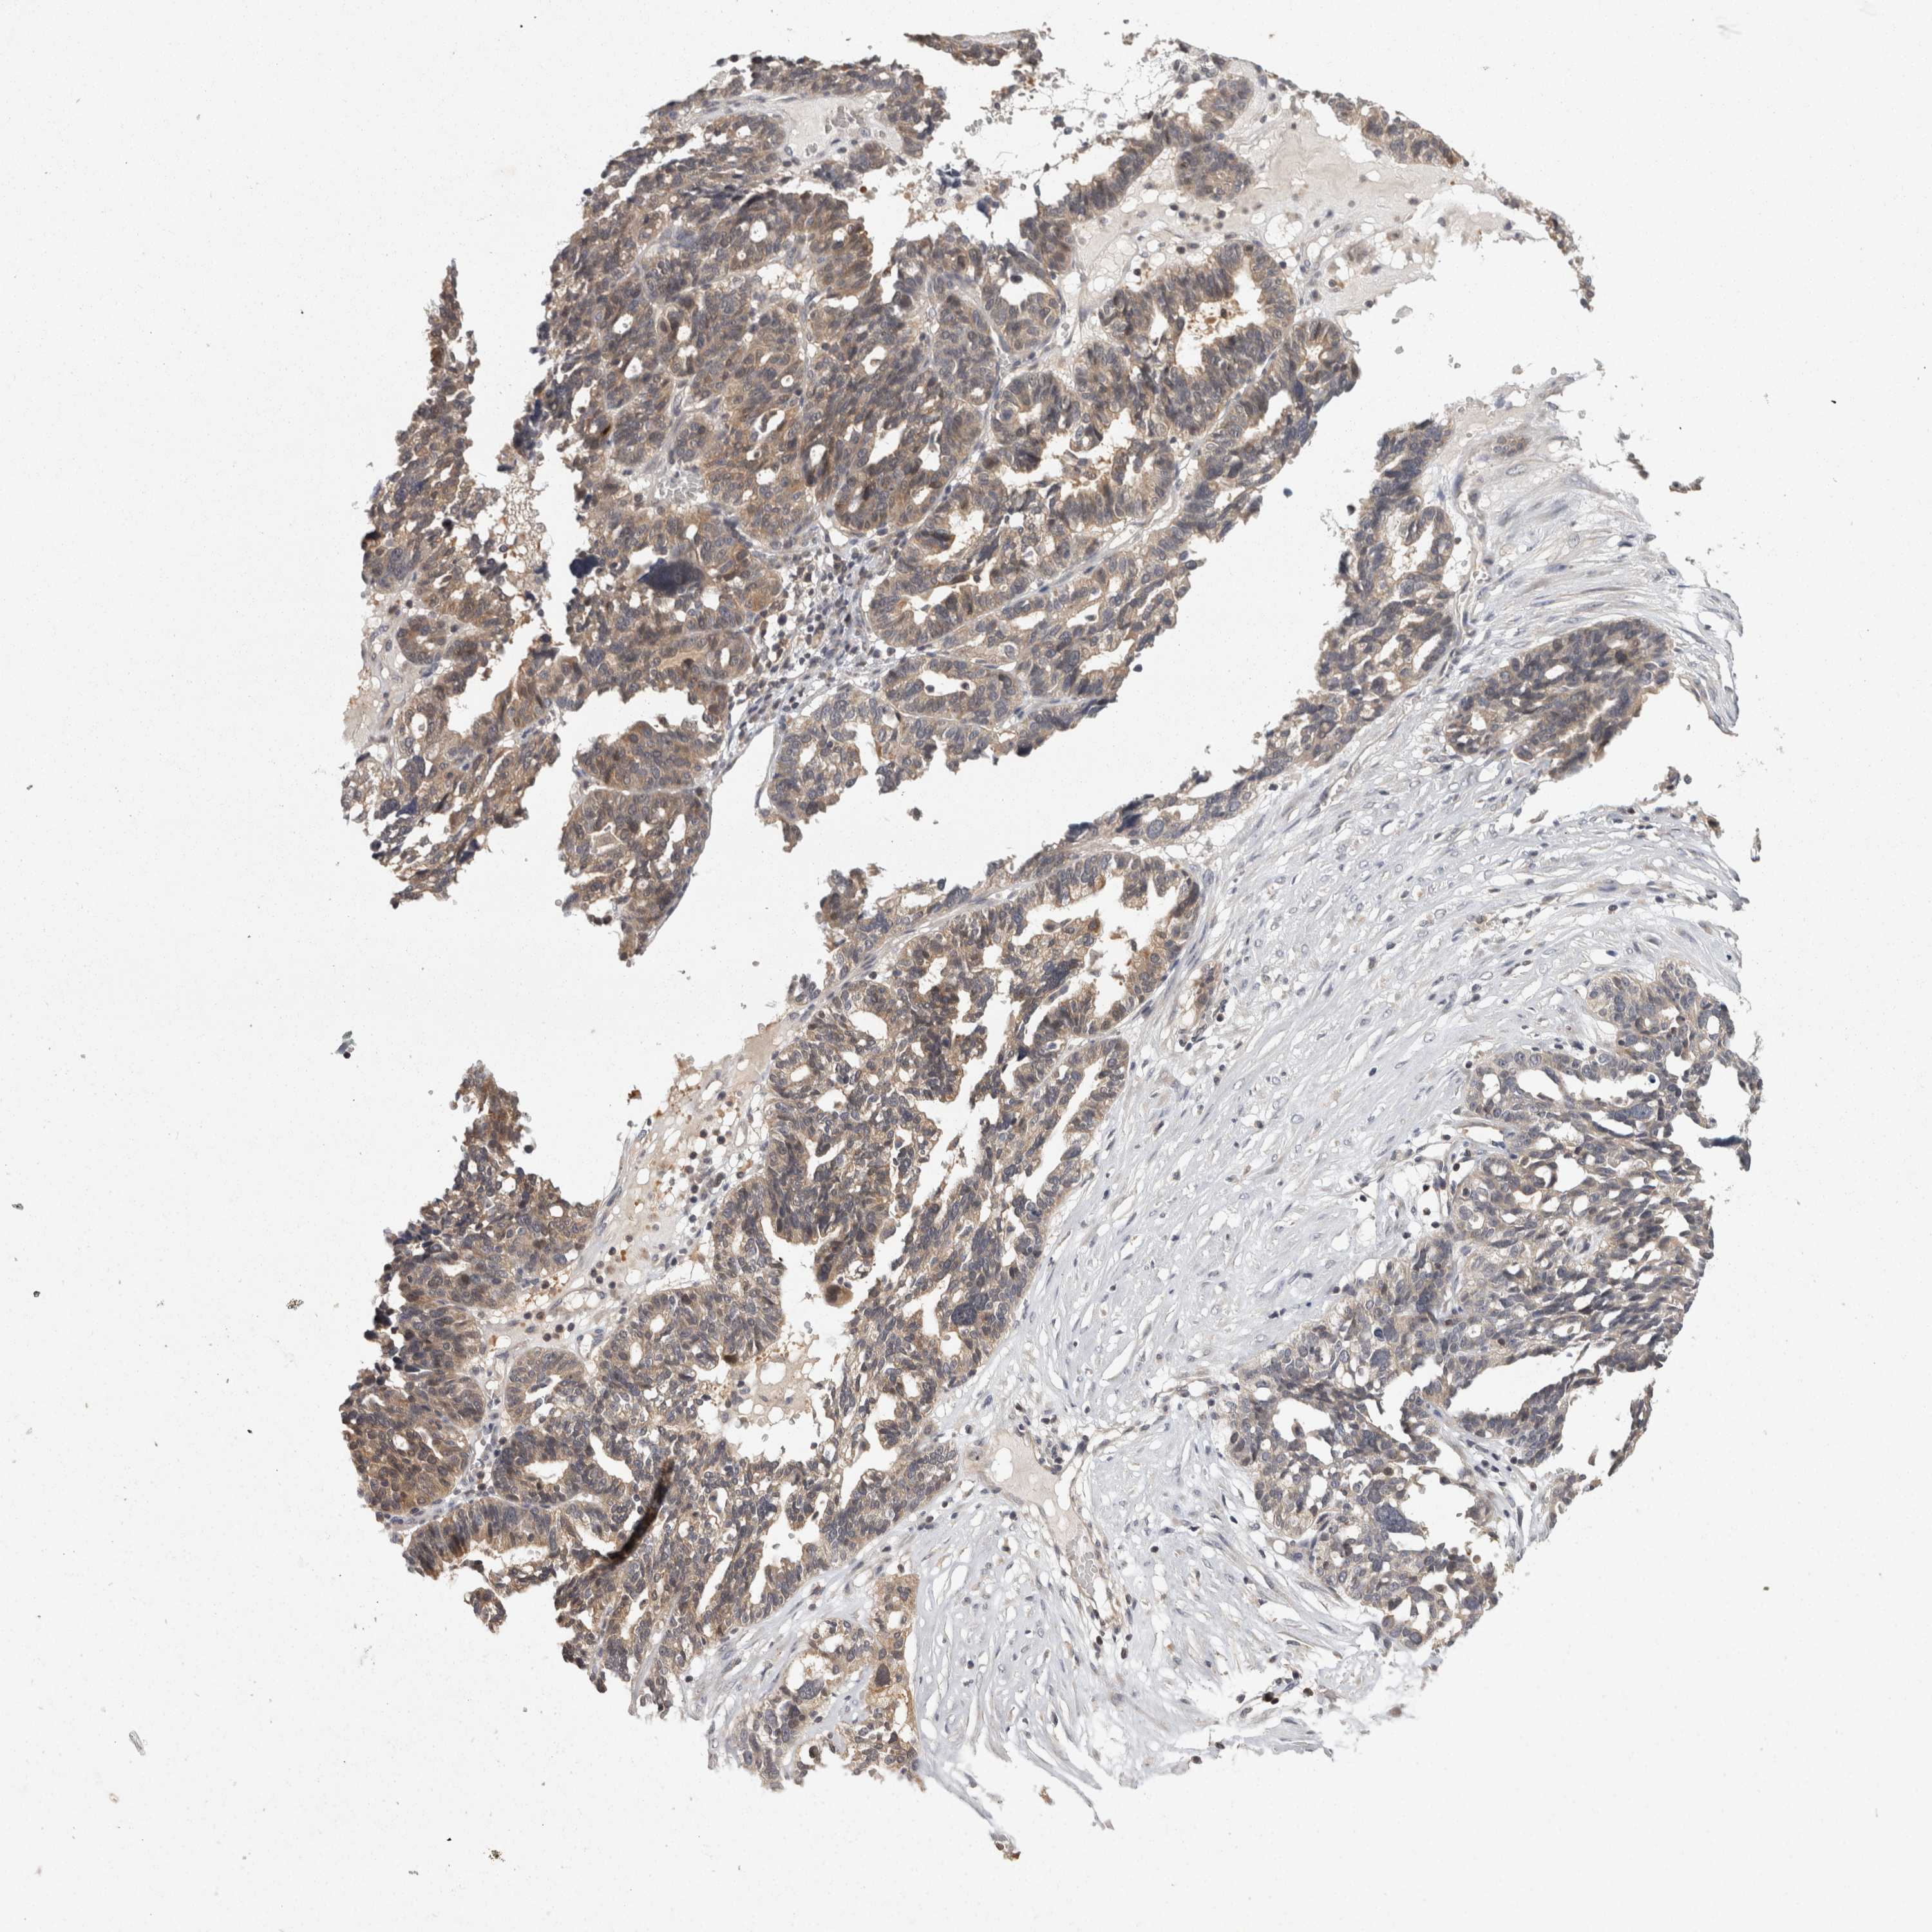

OVARIAN CANCER - Protein expressioni

A mouse-over function shows sample information and annotation data. Click on an image to view it in a full screen mode. Samples can be filtered based on level of antibody staining by selecting one or several of the following categories: high, medium, low and not detected. The assay and annotation is described here.

Note that samples used for immunohistochemistry by the Human Protein Atlas do not correspond to samples in the TCGA dataset.

Antibody stainingi

Antibody staining in the annotated cell types in the current human tissue is reported as not detected, low, medium, or high, based on conventional immunohistochemistry profiling in selected tissues. This score is based on the combination of the staining intensity and fraction of stained cells.

Each image is clickable and will lead to virtual microscopy that enables deeper exploration of all samples and also displays staining intensity scores, fraction scores and subcellular localization as well as patient and tissue information for each sample.

Antibody CAB021106

Cystadenocarcinoma, serous, NOS

Carcinoma, endometroid

Cystadenocarcinoma, mucinous, NOS

Carcinoma, NOS